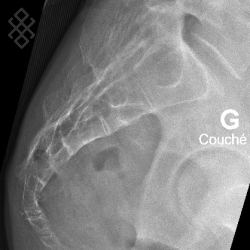

Radiographie du Coccyx

Vous serez installés en position debout puis assise.